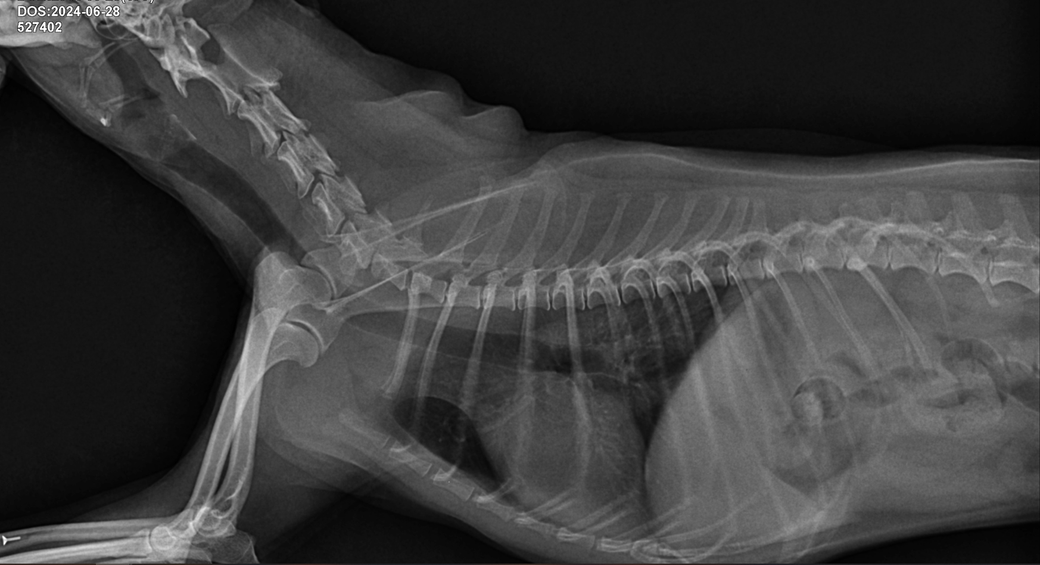

선생님 저희 강아지 허리디스크가 어느정도인가요?

한달에 한번 주기로 깨갱 거리면서 특히나 혼자 붕가붕가하고 나서 그러는데요

허리 디스크가 어느정도 상태인지 그리고 붕가붕가를 평생 못하게해야하는건지.. 알려주시면 감사하겠습니다....

경추와 흉요추부에 디스크 소인이 있는 양상이 관찰되고 있지만 디스크는 엑스레이 사진으로 평가하는 질환이 아닙니다.

척추뼈나 추간판(디스크)에 큰 변화가 있지 않는 이상

방사선 사진만으로 이상 여부를 판단하기 어렵습니다.